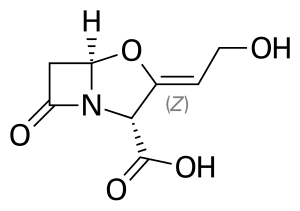

Amoxicillin/clavulanic acid

| Combination of | |

| Amoxicillin | Penicillin antibiotic |

| Clavulanic acid | Beta-lactamase inhibitor |

Amoxicillin/clavulanic acid, also known as co-amoxiclav, is an antibiotic useful for the treatment of a number of bacterial infections.[2] It is a combination consisting of amoxicillin, a β-lactam antibiotic, and potassium clavulanate, a β-lactamase inhibitor.[2] It is specifically used for otitis media, strep throat, pneumonia, cellulitis, urinary tract infections, and animal bites.[2] It is taken by mouth or by injection into a vein.[3]